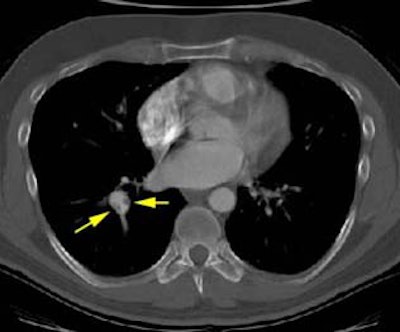

CT scan revealed eccentric thrombus in the right lower lobe pulmonary artery: